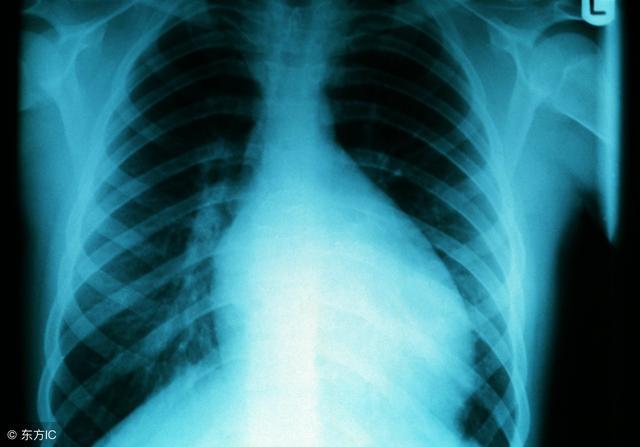

心肌炎怎样治疗?心肌炎是一种常见的,多发的疾病,并且心肌炎会给患者的身体健康造成十分严重的危害。如果不能及时治疗的话,可能还会导致失去宝贵的生命。那么心肌炎怎样治疗呢?